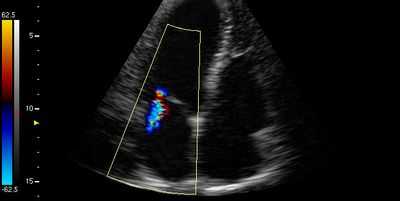

- Острый дефект межжелудочковой перегородки (ДМЖП). Эта патология часто происходит около верхушки сердца и чаще встречается при нижнем инфаркте левого и инфаркте правого желудочков. Нарушение непрерывности МЖП можно увидеть на 2-D эхокардиограмме в апикальной 4-камерной, парастернальной длинной оси и короткой оси. Цветное допплеровское картирование может точно показать дефект. Импульсно-волновой допплер, перемещенный вдоль правой стороны МЖП (парастернальная длинная ось или иногда четырехкамерная проекция), может показать турбулентную струю сброса.

На 2-е и 20-е сутки заболевания с помощью ЭхоКГ определяли количественные показатели ИМР [площадь регургитационного отверстия (SRO мм2), регургитационный объем (RV, мл), фракция регургитации (RF, %)] с использованием комбинации цветового допплеровского картирования проксимального сходящегося потока регургитации (PISA-метод, proximal isovelocity surface area method) и количественной допплер-ЭхоКГ (Q-DE-метод) [1—3].